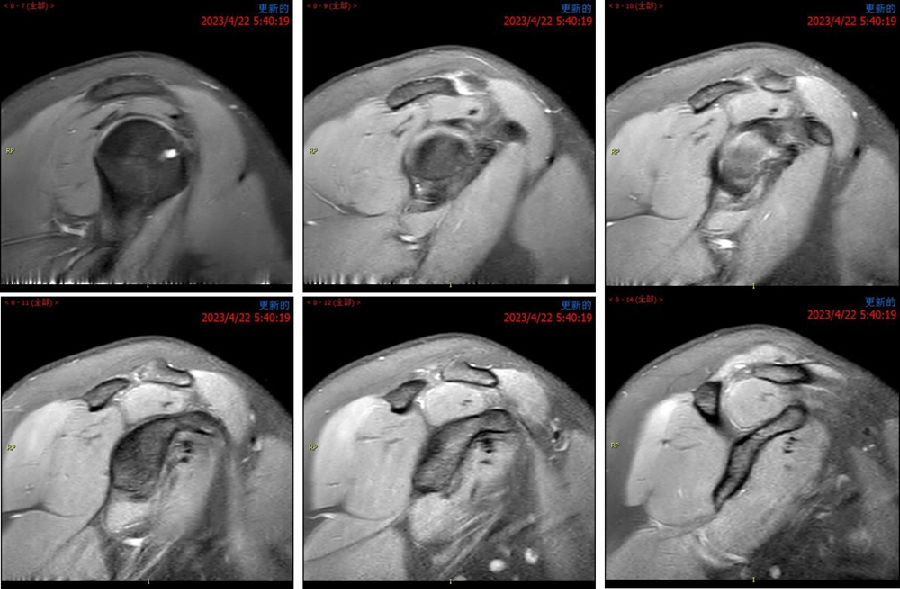

典型病例,苏X,男,36岁。主诉左肩关节反复脱位2年。诊断左肩复发性脱位、左肩胛盂骨折(骨性Bankart损伤)、左肱骨头Hill-Sachs损伤。

手术方案:左肩关节镜下探查清理、Latarjet术。

图44 术前MRI

图45 CT D=26mm d=8mm(上患侧,下健侧)

图46 CT d/D=30.7% GT=0.83D-d=13.6mm Hill-Sachs损伤I级,骨缺损 >25%